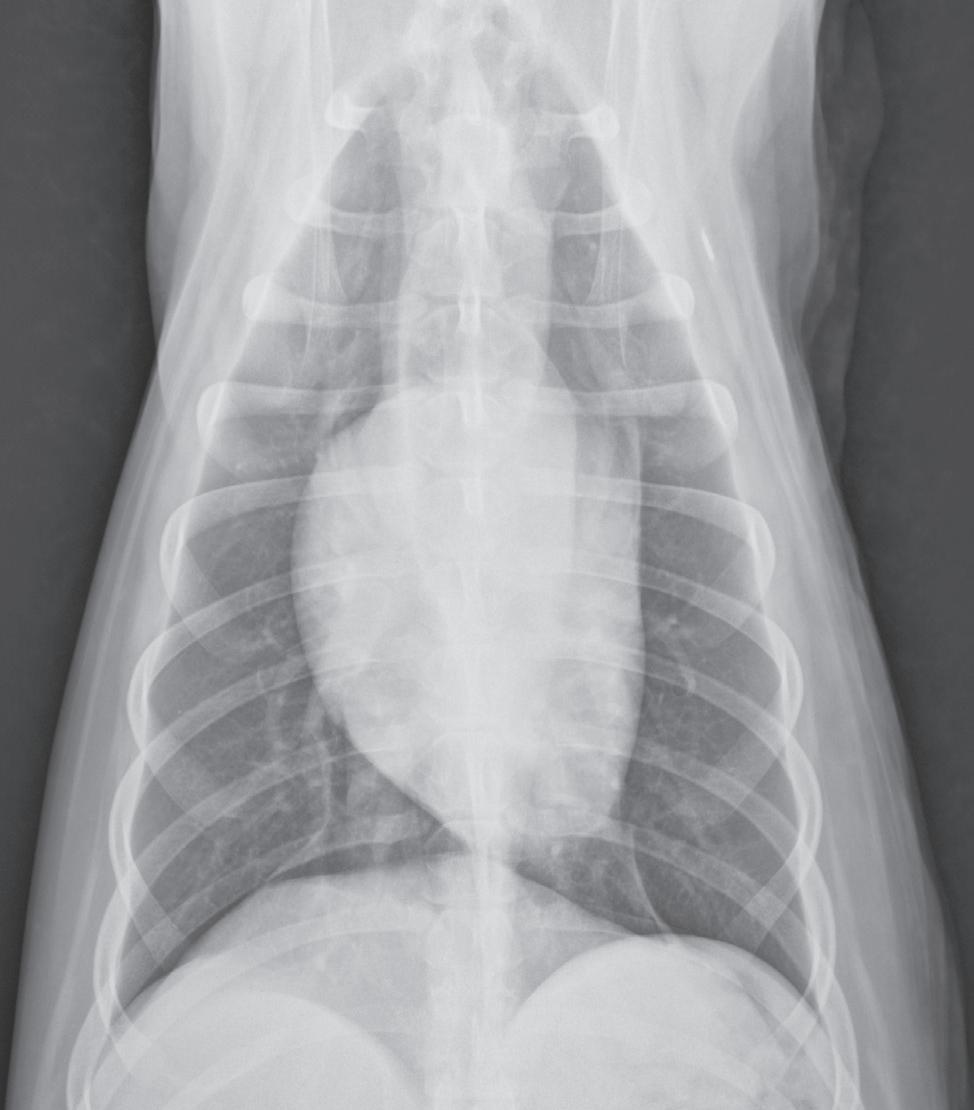

n Lateral images of any body part should be oriented with the cranial or rostral aspect of the body heading to the examiner’s left (Figure 1-2).

Correct orientation of a lateral view of any body part. A lateral view of the thorax is shown here.

1-3. Correct orientation of a ventrodorsal view of the head, spine, thorax, abdomen, or pelvis. A ventrodorsal view of the thorax is shown here. This same orientation would be used if the image were a dorsoventral view.